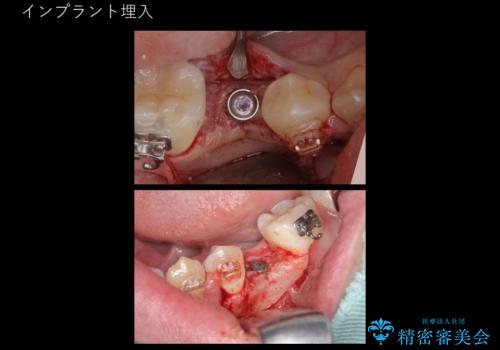

生まれつき歯が少ない 20代でインプラント治療

- 左下の奥歯が生まれつき歯が少ない患者様です。

健康な歯を削らずに歯を入れたいとのことでした。

歯がなかった時期に隣の歯が移動してすき間があったため、部分的な矯正治療を行い、インプラントを入れるすき間を確保しています。

- 68.2万円 内訳: 部分矯正治療 22万円、インプラント 22万円、チタンカスタムアバットメント11万円、ジルコニアクラウン 11万円、矯正用シリンダーテック(仮歯) 2.2万円費用は治療当時の料金となります

矯正治療で歯を移動して得られたすき間はインプラントのクラウンで動かないようにできるためです。